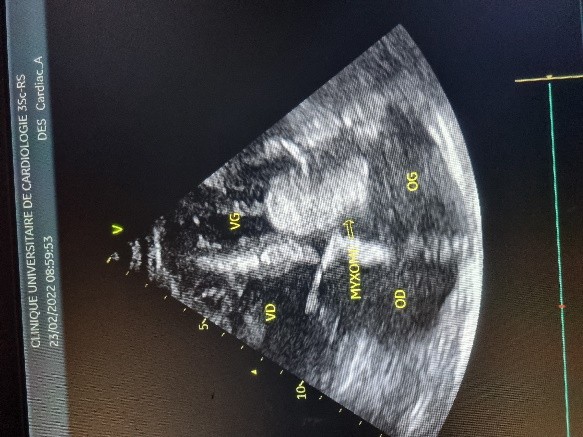

L’électrocardiogramme notait un rythme sinusal régulier avec une fréquence cardiaque à 83 bpm, des anomalies de la repolarisation en antéro septal à type d’ondes T biphasiques et en inférieur à type d’ondes T négatives asymétriques. La biologie était normale. L’échocardiographie (transthoracique et transœsophagienne) retrouvait les mêmes caractéristiques avec une masse appendue à la face atriale de la grande valve mitrale, obstruant partiellement l’orifice mitral et mesurant 49mm ×27 mm. Elle faisait protrusion dans le ventricule gauche en diastole (Figures 5 et 6). Cette masse était évocatrice d’un myxome de l’oreillette gauche. Le ventricule gauche n’était pas dilaté (DTDVG= 46mm), avec une fraction d’éjection systolique à 74% au Simpson biplan. Les pressions de remplissage du ventricule gauche étaient élevées. L’oreillette gauche était dilatée (VOG= 43mL/m²). Les cavités droites n’étaient pas dilatées. La fonction ventriculaire droite était normale (TAPSE= 24mm). On notait une hypertension pulmonaire avec PAPS =75mmHg, VmaxIT= 4,18 m/s. La veine cave inférieure était fine et compliante.

Figure 3 (a et b) : Echocardiographie transthoracique en mode bi dimensionnel montrant le myxome de l’oreillette gauche appendu au septum inter atrial vu en mode 4 cavités (a) et 2 cavités (b) chez un patient de 54 ans (Cas clinique n°2). VG= ventricule gauche; OG= oreillette gauche; OD= oreillette droite ; VD= ventricule droit.

Figure 4 (a et b): Echocardiographie transoesophagienne en bi dimensionnelle, incidence 4 cavités plan oblique à 135° montrant un myxome appendu au septum inter atrial (Cas clinique n°2). VG= ventricule gauche ; OG= oreillette gauche ; VD= ventricule droit.